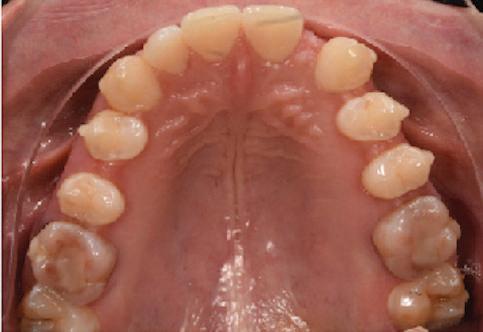

Dental Tribune Bulgarian Edition / октомври 2022 г.16 клиничен случай с алайнери Г орният латерален ре зец е вторият найчесто вродено липсващ зъб.1,2 Поради разполо жението му във видимата зона на усмивката лечение то на подобни случаи нала га мултидисциплинарен под ход, целящ отличен функцио нален и естетичен резултат. Налице са няколко лечебни мо далности, свързани с различ но разпределение на място то: първият вариант е орто донтско отваряне на място и възстановяване на липсва щия зъб с конструкция, под държана от съседните зъби3 или от имплант4, докато при втория подход разстоянията се затварят и премоларът заема мястото на канина.5 Изборът на лечебен подход трябва да бъде направен съв местно от зъболекар и паци ент въз основа на очакванията на последния и предвиди мостта на лечението. Множе ство фактори влияят върху това решение, като напри мер типа малоклузия, размера, формата и цвета на кучеш ките зъби6, оклузалните вза имоотношения (овърджет и овърбайт), лицевия профил, дължината на зъбната дъга и несъответствията в разме ра на зъбите.7 В настоящата публикация се разглежда случаят на жена в зряла възраст с вродена лип са на горен ляв латерален резец. Бяха приложени про зрачни алайнери за отваряне на място за единичен им плант и бяха постигна ти функционална оклузия и отлична естетика. ПРЕДСТАВЯНЕ НА СЛУЧАЯ Диагноза Пациентката бе на 32 годи ни, когато лечението започна, и първоначалното ѝ състоя ние бе следното (фиг. 1–3): липсващ горен ляв латерален резец; клас II, подклас I малоклузия; отклонение на горната сре динна линия вляво; Доклад на клиничен случай ЛЕЧЕНИЕ С АЛАЙНЕРИ НА ПАЦИЕНТ С АГЕНЕЗИЯ НА ЛАТЕРАЛЕН РЕЗЕЦ Д-р Iro Eleftheriadi и д-р Christodoulos Laspos, Гърция и Кипър Фиг. 1a–h Предоперативни лицеви и интраорални снимки. Фиг. 2a–e Дигитални модели преди началото на лечението. Фиг. 3 Панорамна снимка преди лечението. Фиг. 1a Фиг. 1d Фиг. 1f Фиг. 2a Фиг. 2d Фиг. 2b Фиг. 2e Фиг. 3 Фиг. 2c Фиг. 1b Фиг. 1e Фиг. 1g Фиг. 1h Фиг. 1c

Dental Tribune Bulgarian Edition / октомври 2022 г. 17клиничен случай с алайнери леко струпване в долната че люст; несъответствие по Болтън (мандибуларен излишък от 3.06 мм във фронталната зона и общо 1.47 мм); издължено лице с лицева аси метрия; конвексен профил с ретруди рана долна челюст и проми нентен нос. На мястото на зъб #46 бе на лице имплант, а зъби #16 и 26 са ендодонтски лекувани. Тези зъби бяха асимптоматич ни, затова бе взето решение да се прави релечение само при нужда. Мъдреците липсваха. Анализът на телерентгеногра фията (фиг. 4) показа ретрог натна мандибула (SNB: 74.2°) и нормална инклинация на резците както в

Цели на лечението и лечебен план Целите на лечението бяха следните: нивелиране и подреждане на зъбите и в двете зъбни дъги; отваряне на пространство за липсващия латерален резец; коригиране на отношенията при канините и моларите до клас I; и корекция на отклонението на срединната линия. Лечебният план включваше: корекция на отношенията при кучешките зъби и мола рите до клас I с дистализира не на максилата; отваряне на пространство в областта на #22 за поставя не на единичен имплант; корекция на срединната ли ния; и създаване на място за раз ширяване на зъб #12 и апрок симална редукция в долната челюст с цел подобряване на несъответствието по Болтън и осигуряване на подобра оклузия. Изпълнение на лечебния план Този случай бе изпълнен със системата за алайнери Invisalign (Align Technology). Одобреният първоначален лечебен план предвиждаше 49 алайне ра с дистализиране на задни те горни зъби до клас I (прибли зително с около 3.5 мм; фиг. 5). За бъдещия имплант в областта на липсващия латерал бе планирано пространство от 6.5 мм, докато във фронталния сегмент на долната челюст бе предвидена апроксимална редук ция. В дясната страна бутон за ластици клас II бе поставен на зъб #47 вместо на зъб #46, за да не се увреди короната на импланта. Понеже пациентката жи вееше в чужбина,